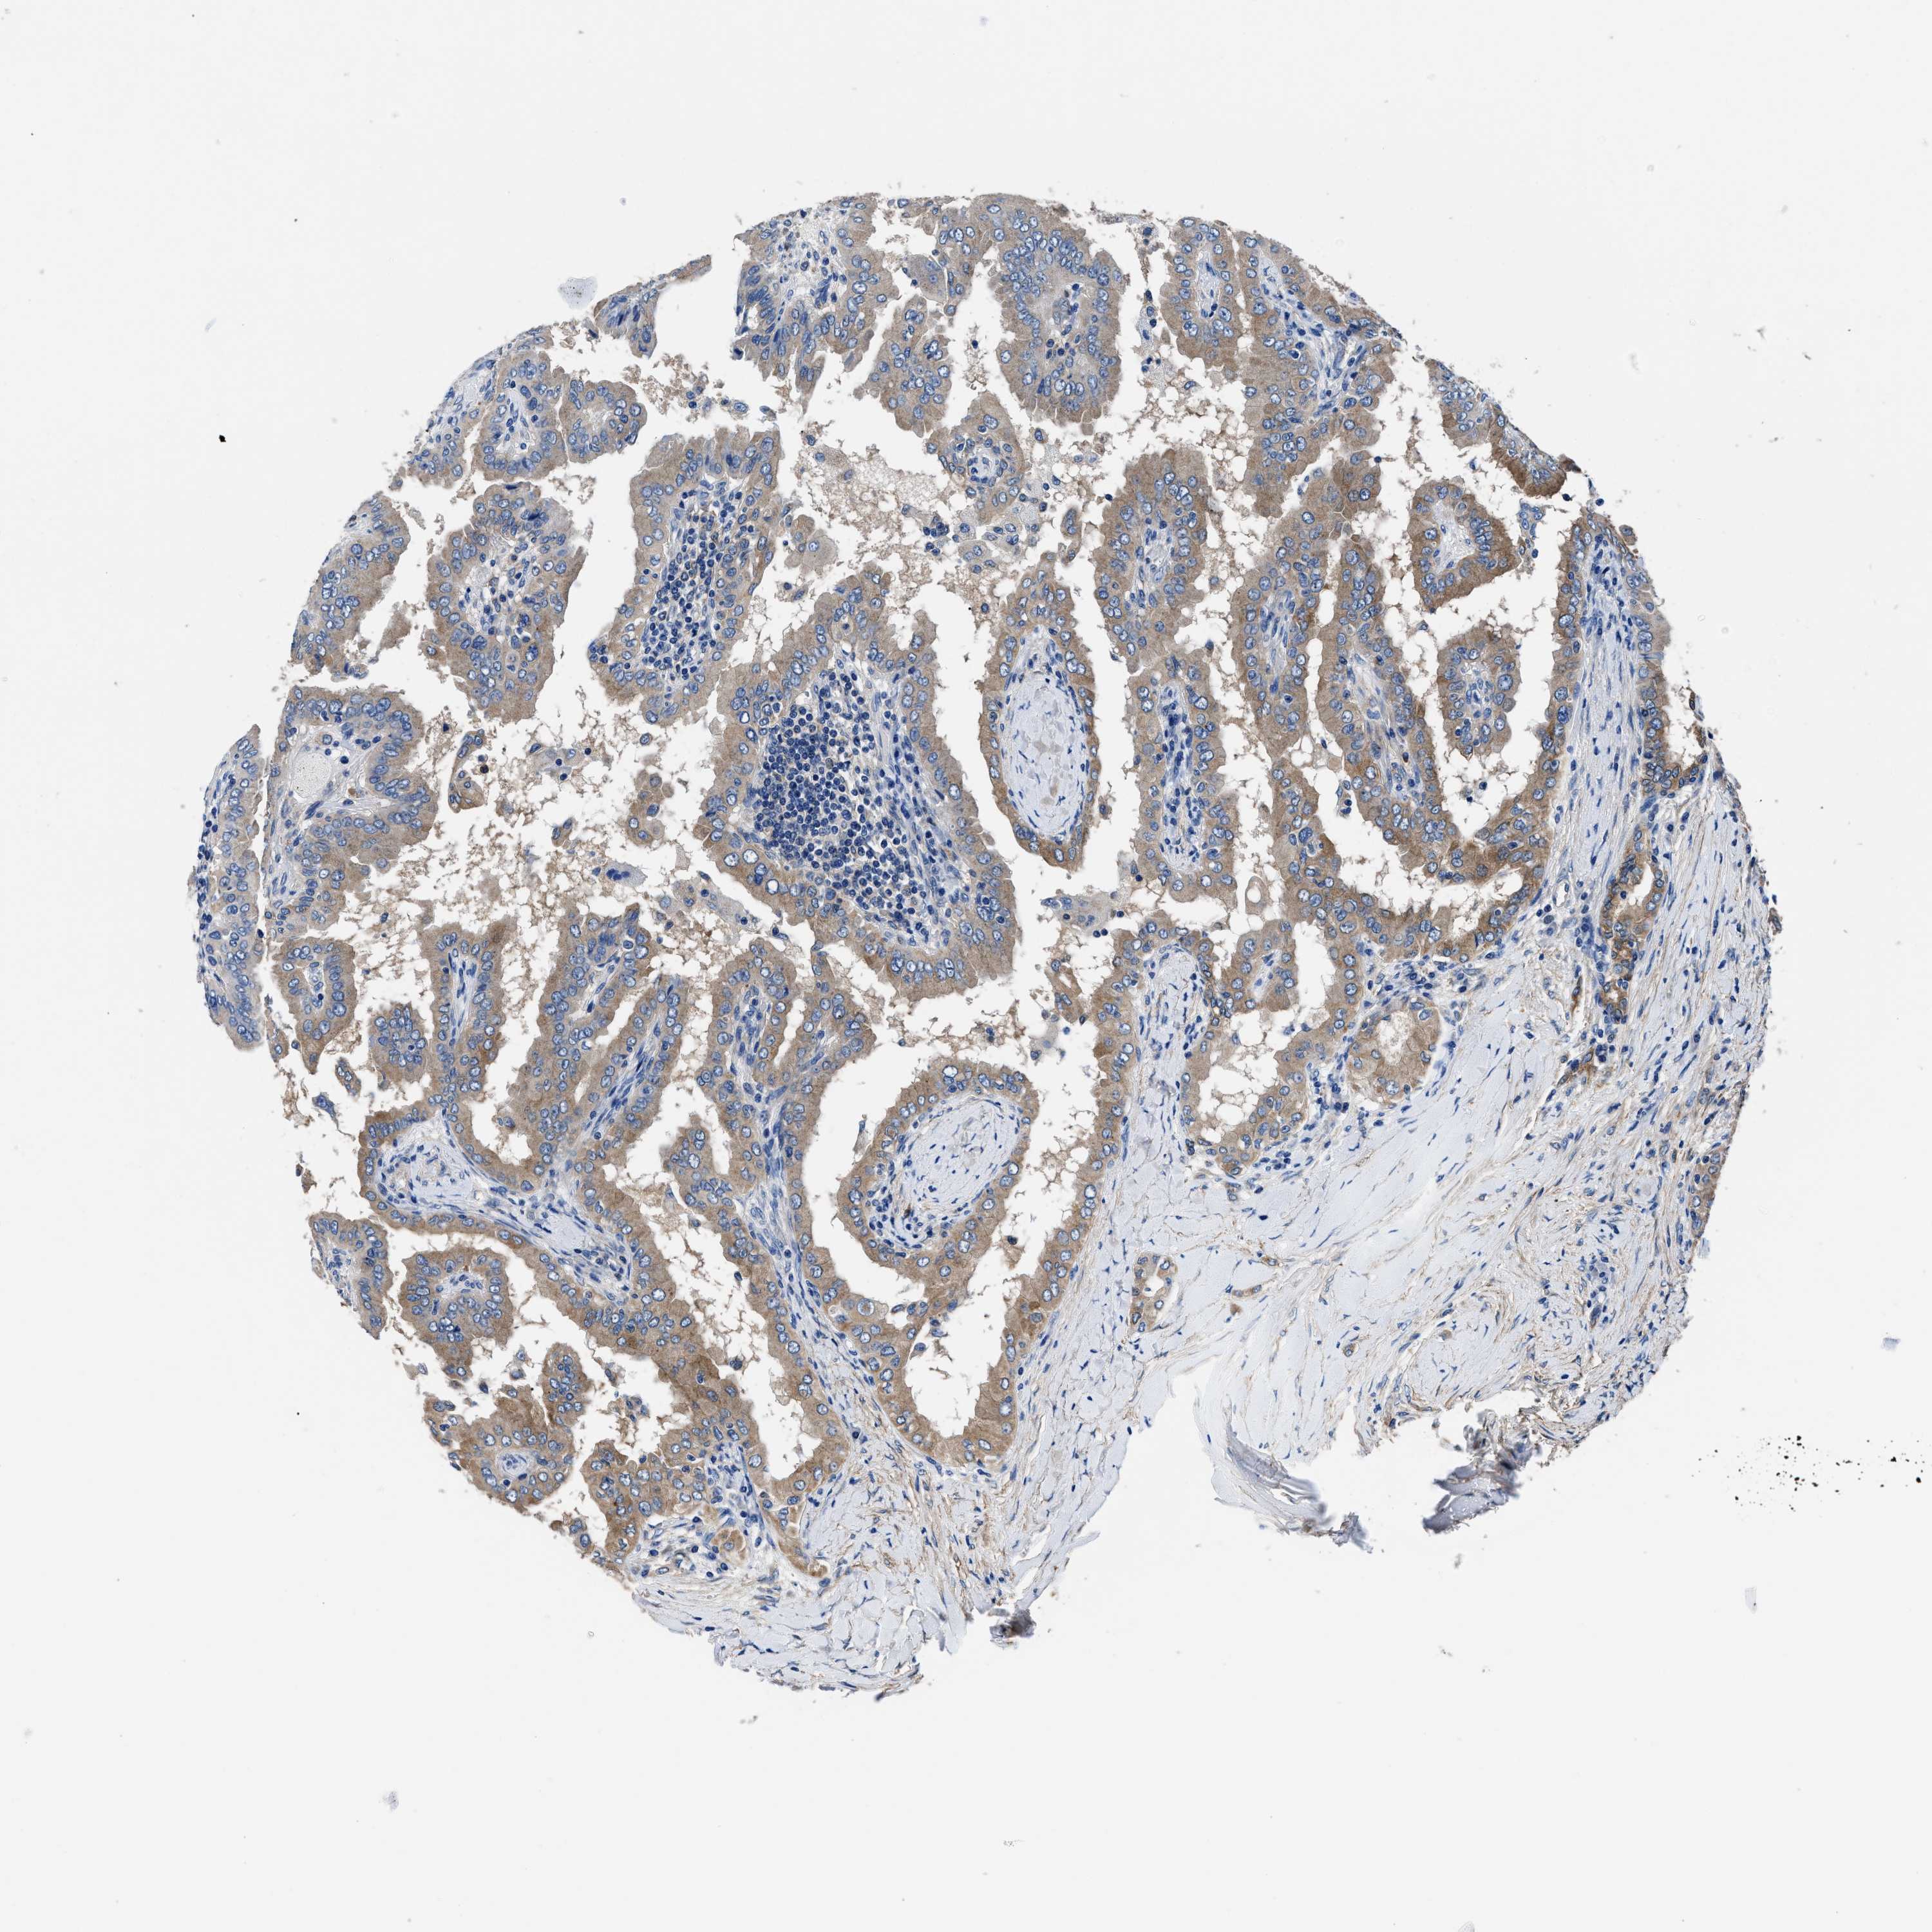

THYROID CANCER - Protein expressioni

A mouse-over function shows sample information and annotation data. Click on an image to view it in a full screen mode. Samples can be filtered based on level of antibody staining by selecting one or several of the following categories: high, medium, low and not detected. The assay and annotation is described here.

Note that samples used for immunohistochemistry by the Human Protein Atlas do not correspond to samples in the TCGA dataset.

Antibody stainingi

Antibody staining in the annotated cell types in the current human tissue is reported as not detected, low, medium, or high, based on conventional immunohistochemistry profiling in selected tissues. This score is based on the combination of the staining intensity and fraction of stained cells.

Each image is clickable and will lead to virtual microscopy that enables deeper exploration of all samples and also displays staining intensity scores, fraction scores and subcellular localization as well as patient and tissue information for each sample.

Antibody HPA015634

Antibody HPA021506

Staining

High

Medium

Low

Not detected

Intensity

Strong

Moderate

Weak

Negative

Quantity

>75%

75%-25%

<25%

None

Location

Nuclear

Cytoplasmic/membranous

Cytoplasmic/membranous,nuclear

Papillary adenocarcinoma, NOS

Follicular adenoma carcinoma, NOS